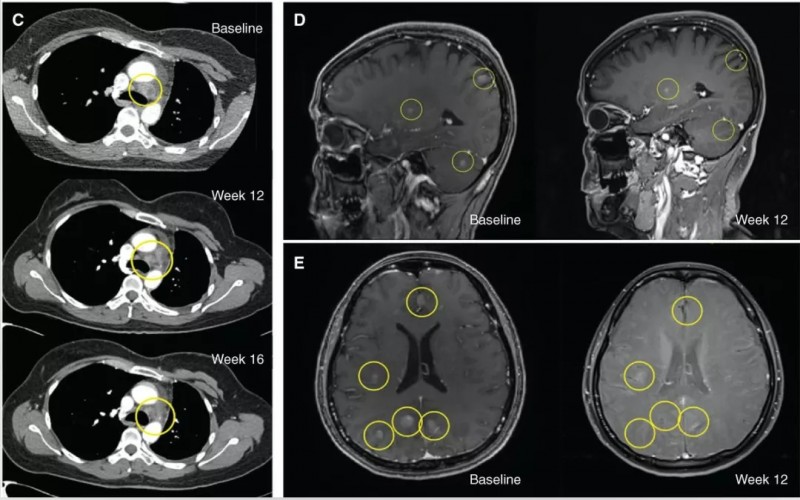

一位ROS1+患者在克唑替尼治疗后出现复发,复查时发现脑部有多个无明显症状的脑转移病灶,于是开始接受每天40–240 mg repotrectinib治疗,在16个月时,肿瘤缩小了40%(PR(−40%))。